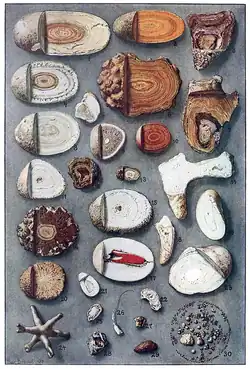

Einteilung

Am gebräuchlichsten ist die Einteilung der Nierensteine nach ihrer äußeren Form oder ihrer chemischen Zusammensetzung:

- Klassifikation nach Form:

- Ventilsteine

- Hirschgeweihsteine

- Korallensteine

- Ausgusssteine

- Klassifikation nach chemischer Zusammensetzung:

- Calciumoxalat-Steine (65 % Häufigkeit)

- Urat-Steine (Harnsäuresteine, 15 %)

- Magnesiumammoniumphosphat-Steine (Struvit-Steine, 11 %) treten vor allem im Zusammenhang mit Infektionen auf und werden daher auch als Infektsteine bezeichnet.

- Calciumphosphat-Steine (9 %)

- Cystin-Steine (ca. 1 %)

- Xanthin-Steine (1 %)

- Auch Mischformen sind möglich.